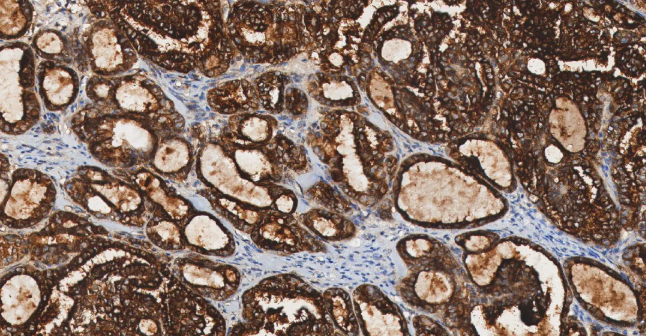

Section.03 结直肠癌标志物

CDX2

CDX2——尾型同源框转录因子 2,属于尾型同源盒转录因子家族。

• 定位:细胞核。

• 功能:CDX2 是肠上皮细胞分化和功能维持的关键转录因子,调控众多肠道特异性基因的表达。

CDX2 在结直肠癌中普遍表达,是确诊肠源性肿瘤的首选标志物。CDX2 具有诊断和预后两方面的意义。一方面它有助于鉴别原发灶不明的转移癌,另一方面在结直肠癌中,其表达状态与分子亚型和预后相关。

图 9. 结直肠癌患者 CDX2 免疫染色结果。